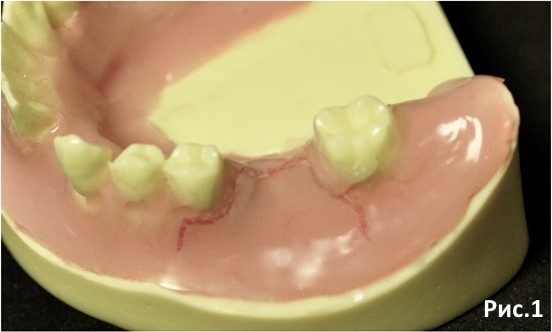

Определяем дизайн лоскута Рис.1